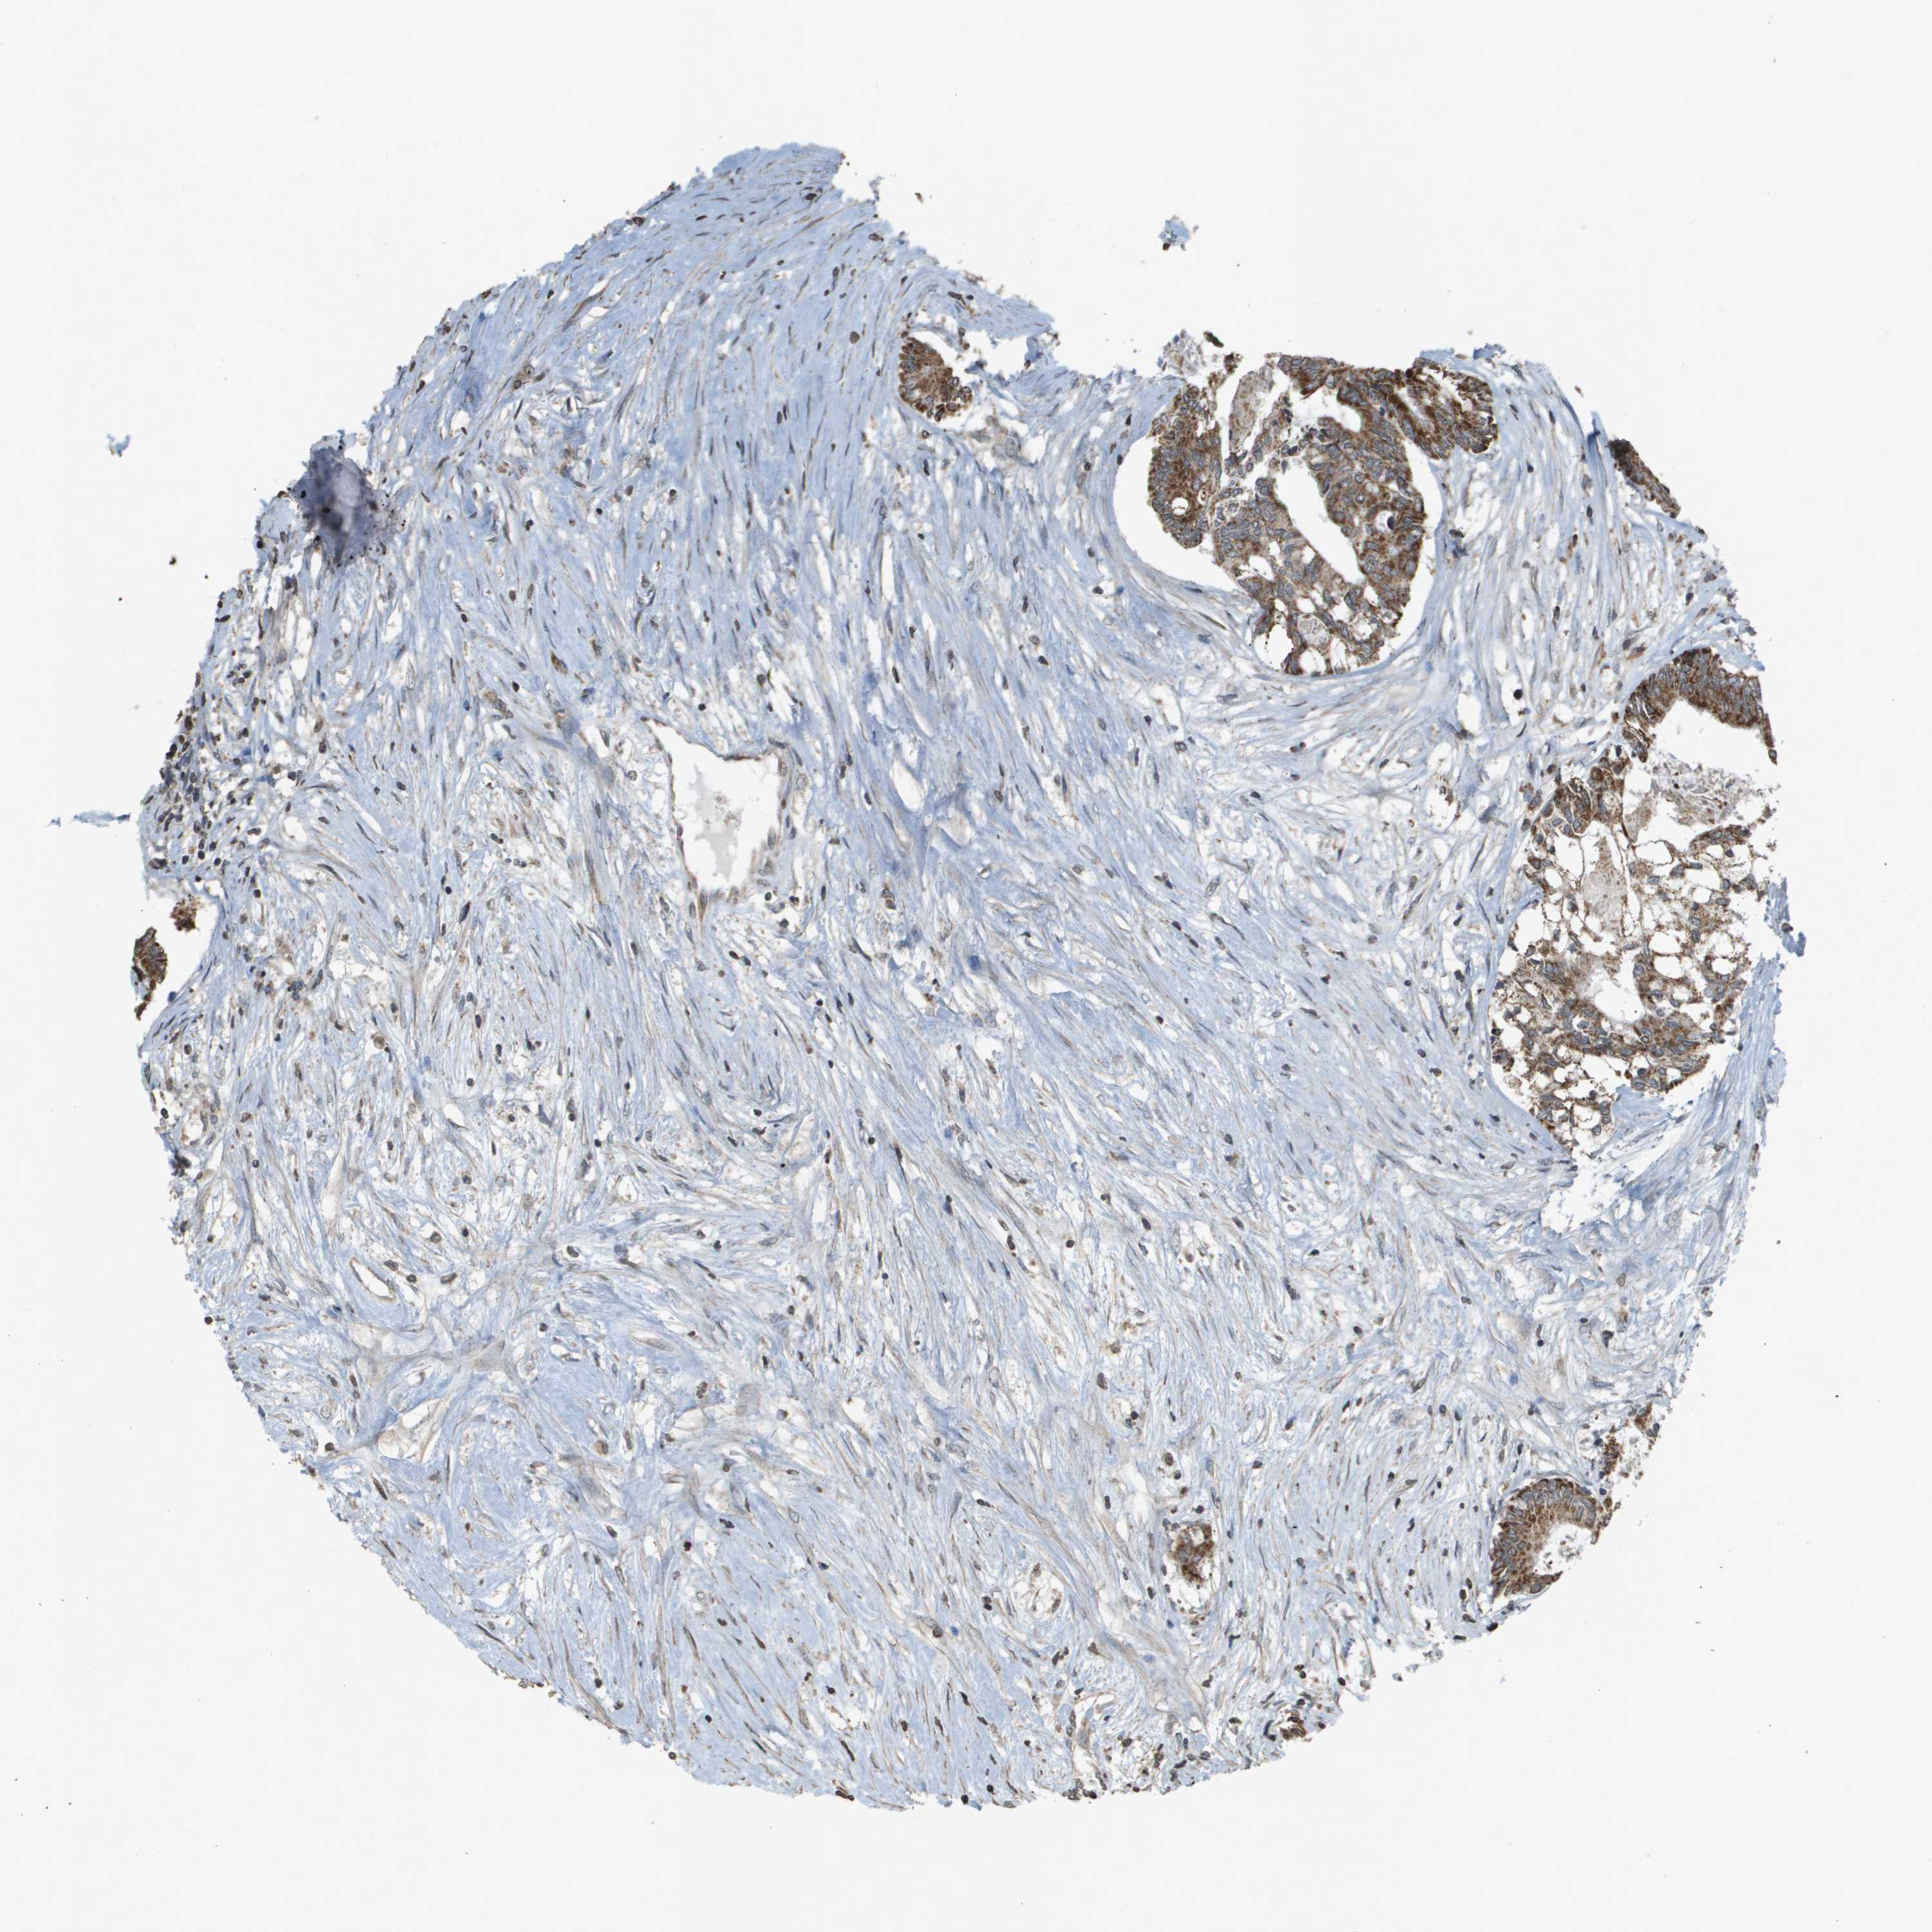

CANCER COLORECTAL CANCER Show tissue menu

Colorectal cancer

Human cancer

Colon adenocarcinoma